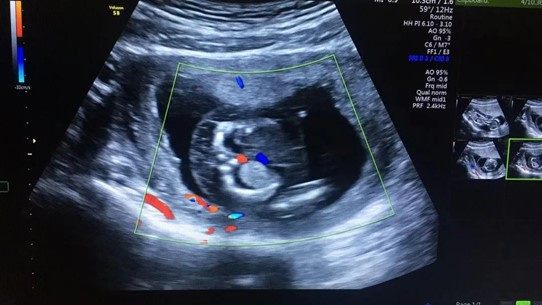

張女士本來(lái)是打算到武漢仁愛(ài)醫(yī)院做完產(chǎn)檢后,就和家人一起回老家過(guò)春節(jié),沒(méi)想到超聲檢查篩查出胎兒全身皮膚水腫,頸部淋巴水囊瘤,雙側(cè)胸腔積液,檢查醫(yī)生立刻叫來(lái)了武漢仁愛(ài)醫(yī)院超聲科主任王娟進(jìn)行再次檢查,確診了胎兒的異常情況。

張女士超聲檢查結(jié)果

“在這種情況下,胎兒需要進(jìn)行染色體的進(jìn)一步檢查,如果染色體有問(wèn)題,就要盡早終止妊娠?!蓖蹙杲榻B,造成這一現(xiàn)象最常見(jiàn)的原因是孩子的染色體異常,在得了淋巴水囊瘤的孩子中,有70%是存在染色體異常的,這個(gè)和年齡相關(guān),年齡越大發(fā)生的概率越高,而這些孩子在早期如果出現(xiàn)了水腫,90%以上都不能夠存活,所以建議盡早終止妊娠。